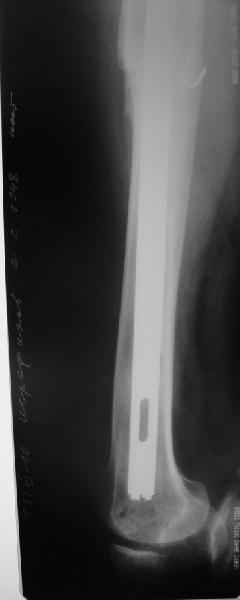

Это сплошной титановый стержень. На дистальном конце отверстия под кондуктор. На другом - канал под ножку глубиной 60 мм, стенки толщиной 2,5-3 мм. И там же продольный пропил, чтобы канал мог адаптироваться к ножке.

Обещанные ранее снимки Заранее спасибо.